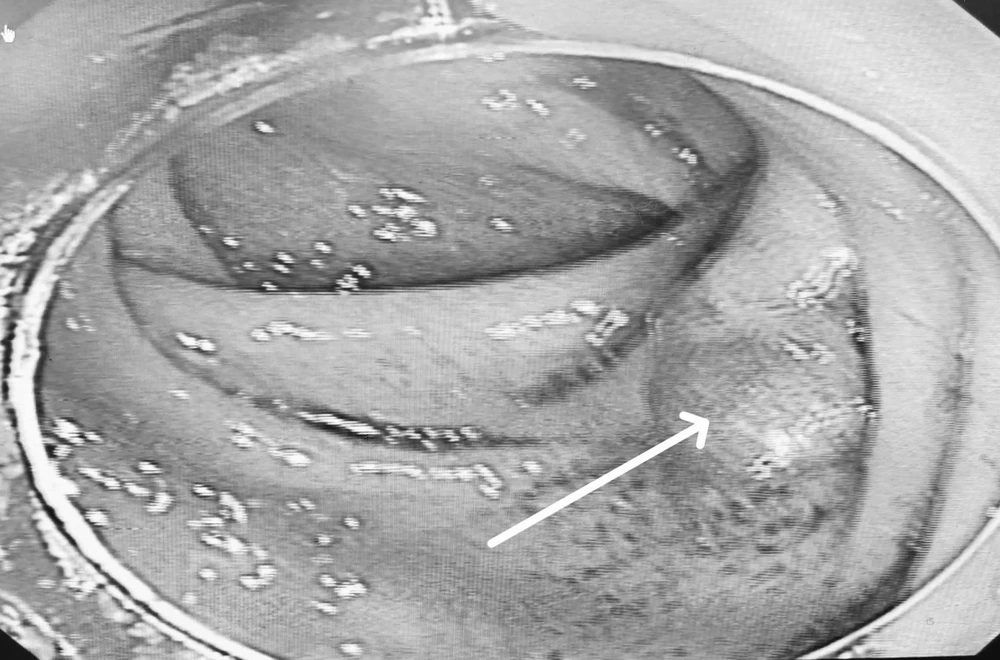

Bệnh nhân nhập viện trong tình trạng đau bụng hố chậu phải kéo dài 3 tuần, kèm tiêu lỏng. Trước đó, nội soi phát hiện polyp lớn (4x5cm) tại manh tràng và nhiều polyp nhỏ rải rác trong đại tràng.

Khối u sùi vùng manh tràng qua nội soi. Ảnh: BVCC.

BS CKI Đỗ Hồng Phong, Khoa Ngoại Tổng hợp cho biết, kết quả CT cho thấy bệnh nhân bị lồng ruột hồi tràng – đại tràng phải do khối u manh tràng.